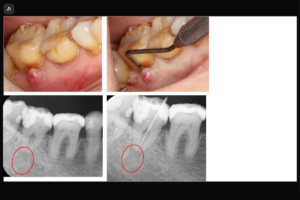

通常の根管治療では治癒しない難症例に対し、外科的にアプローチする治療法です。歯ぐき側から病巣と歯根の先端を切り取る歯根端切除術や、一度歯を抜いて口腔外で修復してから元の位置に戻す意図的再植術があります。マイクロスコープ下で精密に行うことで、本来なら抜歯が必要な歯を保存できる最後の砦となります。